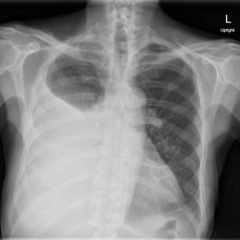

Pleural Effusion, AP Chest Xray JETem 2016

Large Right Pleural Effusion